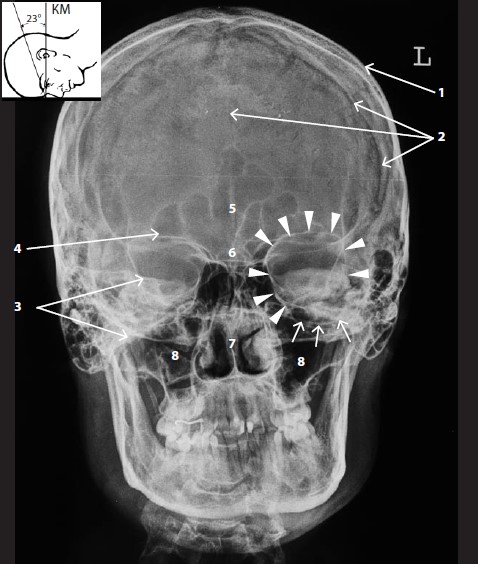

Анатомия детского черепа: Рентгеновские снимки и описание